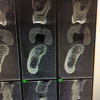

In this case, the patient’s right maxillary first molar had been extracted, and the site was grafted. The periapical radiograph taken after 6 months of healing indicated the presence of dense bone (Figure 11). There was also ample attached mucosa (Figure 12). Impressions were taken, a diagnostic cast was made, and a wax-up of the restoration was placed in the model (Figure 13). To make the radiographic guide for this case, a silicone putty index was created over the diagnostic wax-up, as described earlier. A panoramic radiograph and a CBCT scan (Figure 14) were taken with the radiographic guide in place; the guide post in the index can clearly be seen.

Fig 14. Panoramic radiograph and CBCT scan taken with radiographic guide in place.

Figure 14